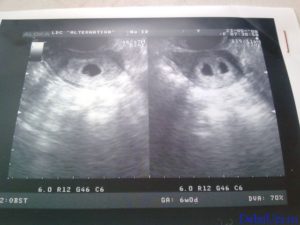

Узи двойни при беременности: фото на ранних сроках в 5-6 недель и позже

Определение двойняшек и близнецов осуществляется таким продуктивным методом исследования, как УЗИ. Этот вид обследования обеспечивает информацией о месте расположения ребенка, имеется ли многоплодная беременность и др.

Как правило, двое эмбрионов четко определяют на УЗИ с самых ранних недель — 5-7. Позже врач способен это определить и без применения ультразвуковой диагностики. Двойняшек можно выявить по такому признаку, как увеличенный размер матки, уже с ранних сроков, а медицинская диагностика с применением ультразвука покажет двух детей только на 1 скрининге — в 10-14 недель.

Двойняшки покажутся на УЗИ уже с 5 недели

Следовательно, наличие двойняшек в утробе выявляется посредством ультразвука уже через месяц после зачатия, на снимке они выглядят как 2 образования темного цвета внутри полости матки (см. фото УЗИ-обследования двойни ниже).

Считается, что точно увидеть несколько эмбрионов, можно только при помощи УЗИ. На каком сроке определяют многоплодную беременность? Специалист может увидеть данный факт в 5-6 недель. Но, как правило, ее диагностируют во время первого скрининга в 12 недель.